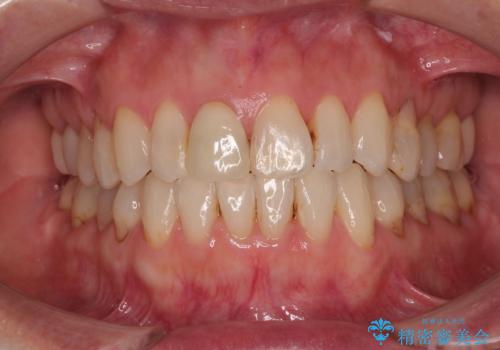

目立つ八重歯を非抜歯矯正で整える 目立たないワイヤー矯正

担当医 藤巻太一朗